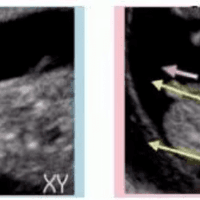

NT值(Nuchal Translucency)是孕妇在孕早期进行孕检时常规检测的一个参数,用于评估胎儿是否存在染色体异常或其他先天性疾病的风险。NT值是通过超声波检查测量胎儿颈部后方的透明层厚度得出的结果。在进行NT值检测时,医生通常会参考孕妇的年龄、孕周数以及其他因素来判断胎儿的健康情况。NT值1.2mm是什么意思?一般来说,NT值在1.2mm范围内被认为是正常的。NT值越小,代表胎儿颈部后方...

问题描述:我现在怀孕已经13周了,上次产检的时候医生说13周的时候可以做一个nt检查,好筛查一下胎儿有没有畸形或是心脏病之类的问题,所以这次我就打算加一个nt检查的项目,在去医院检查之前,我想先在网上问一下正常情况下这个检查的参考值一般是多少啊?最佳回答:13周孕妇的NT检查正常参考值一般在2.5mm以下。NT检查是胎儿颈项透明带的厚度,可以在孕期11周到13周+6天之间进行检测,是孕期非常重要的...